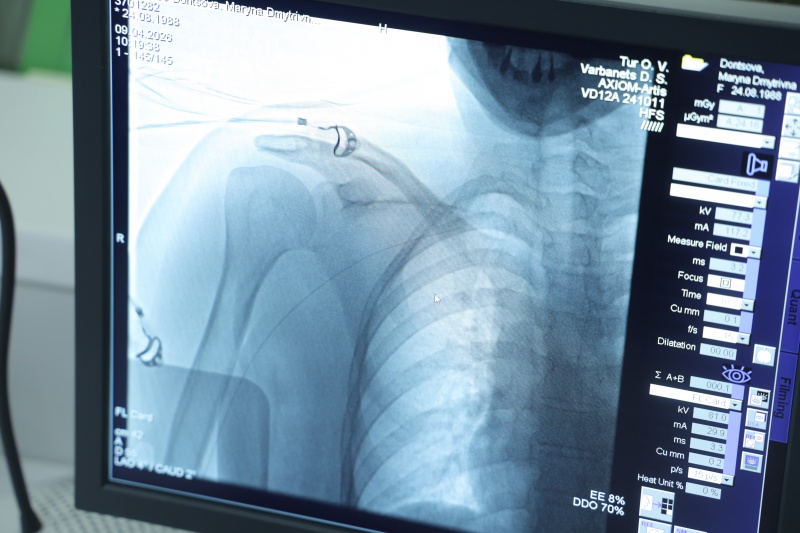

Операция, которую вы сейчас видите – это тоже хирургическое вмешательство, но малоинвазивное (с минимумом разрезов ред.). Сейчас мы с вами разговариваем в операционном отделении. Мы находимся возле изолированного помещения, где за защитным стеклом видно, как врачи проводят стентирование (когда в суженный сосуд ставят маленький каркас стент, чтобы расширить его и восстановить нормальный кровоток. Обычно сосуды сужаются из-за атеросклеротических бляшек ред.)

Врачи, медсестры, одеты в специальные защитные халаты. Это бережет персонал от ионизирующего облучения, поскольку вмешательство проводится под рентгеновскими лучами. Для пациента это тоже не очень приятно и комфортно. Но для пациента, я надеюсь, это единственный такой опыт, в то время как для врачей это может быть и 10-15 раз в день.

В операционной центра кардиологии и кардиохирургии проводят операции стентирования под рентгенологическим контролем (фото: РБК-Украина)

Такие операции как стентирование, шунтирование для вас как для интервенционного кардиолога это уже рядовые процедуры? У вас в центре таких вмешательств делают много. Вот мы с вами находимся в смотровой комнате, а по обе стороны от нас за защитным стеклом идет сразу две таких процедуры.